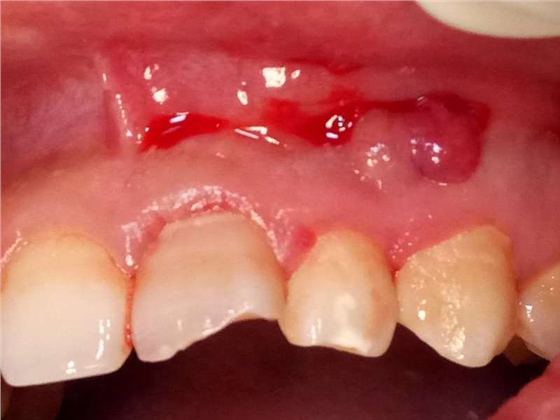

死髓牙2度,沒保留價值了,外傷造成的外吸收,即使到充也容易出問題。和患者溝通,要求做種植,用了兩個骨膠原,側切、尖牙沒事,側切做了一次根充